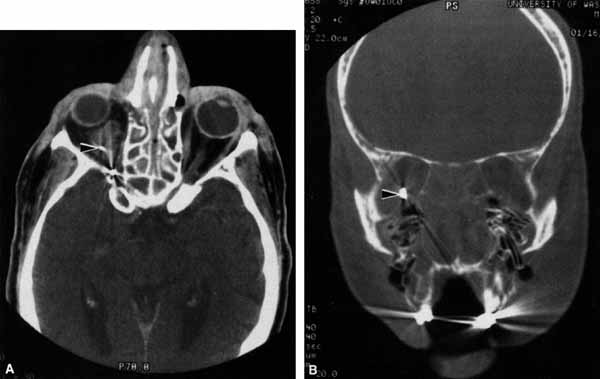

Pupillary dilation and reduction of accommodation occur when parasympathetic innervation to the globe is damaged. When the damage occurs at or distal to the ciliary ganglion, Adie's pupil results. The pupil contracts poorly to light but better to accommodation. The pupil movements are slow and poorly coordinated (vermiform). Generally there is a reduction in accommodation range. The pupil in such cases develops a supersensitivity to parasympathomimetics such as 0.1% pilocarpine. Orbital trauma, inflammation, and intraocular laser treatment may result in Adie's pupil. Deep orbital dissection lateral to the optic nerve in the region of the ciliary ganglion or around the anterior optic nerve where the short ciliary nerves run may also produce Adie's pupil. The denervation may only be sectoral, resulting in an abnormally contoured pupil which demonstrates slow tonic contracture only in the involved sector. Because the parasympathetics have diverged from cranial nerve III prior to entering the ciliary ganglion, pupillary dilation which contracts with 0.1% pilocarpine is not usually associated with neurogenic ophthalmoplegia (Fig. 19).

Fig. 19 A. A patient underwent endoscopic exploration of the right ethmoid and maxillary sinus for persistent epistaxis. Postoperatively the patient demonstrates right proptosis, restricted extraocular movements of the right eye, and a dilated right pupil. Instillation of 0.1% pilocarpine resulted in miosis on the right and no change on the left. Computed tomography (CT) shows a vessel clip lateral to the optic nerve (arrow), near the position of the ciliary ganglion. B. Coronal CT scan showing the clip lateral to the optic nerve (arrow).

Damage to parasympathetic fibers proximal to the ciliary ganglion also results in a dilated pupil but without the susceptibility to 0.1% pilocarpine. Trauma, surgery, inflammation, and intracranial aneurysms may produce a dilated pupil. Damage to the parasympathetics proximal to the ciliary ganglion is usually associated with ptosis and third cranial nerve ophthalmoplegia.